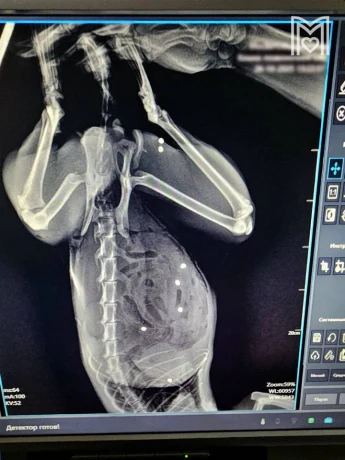

Пушистого пациента осмотрел хирург Евгений Цыбин, который выяснил, что у того пробит кишечник в 24-х местах и в двух местах - селезенка, также пули попали в грудную клетку и мышцы бедра. Доктор немедленно приступил к операции, которая заняла три часа. После Тимофей пошел на поправку, и сегодня его здоровье уже вне опасности.

Фото: Мосветобъединение